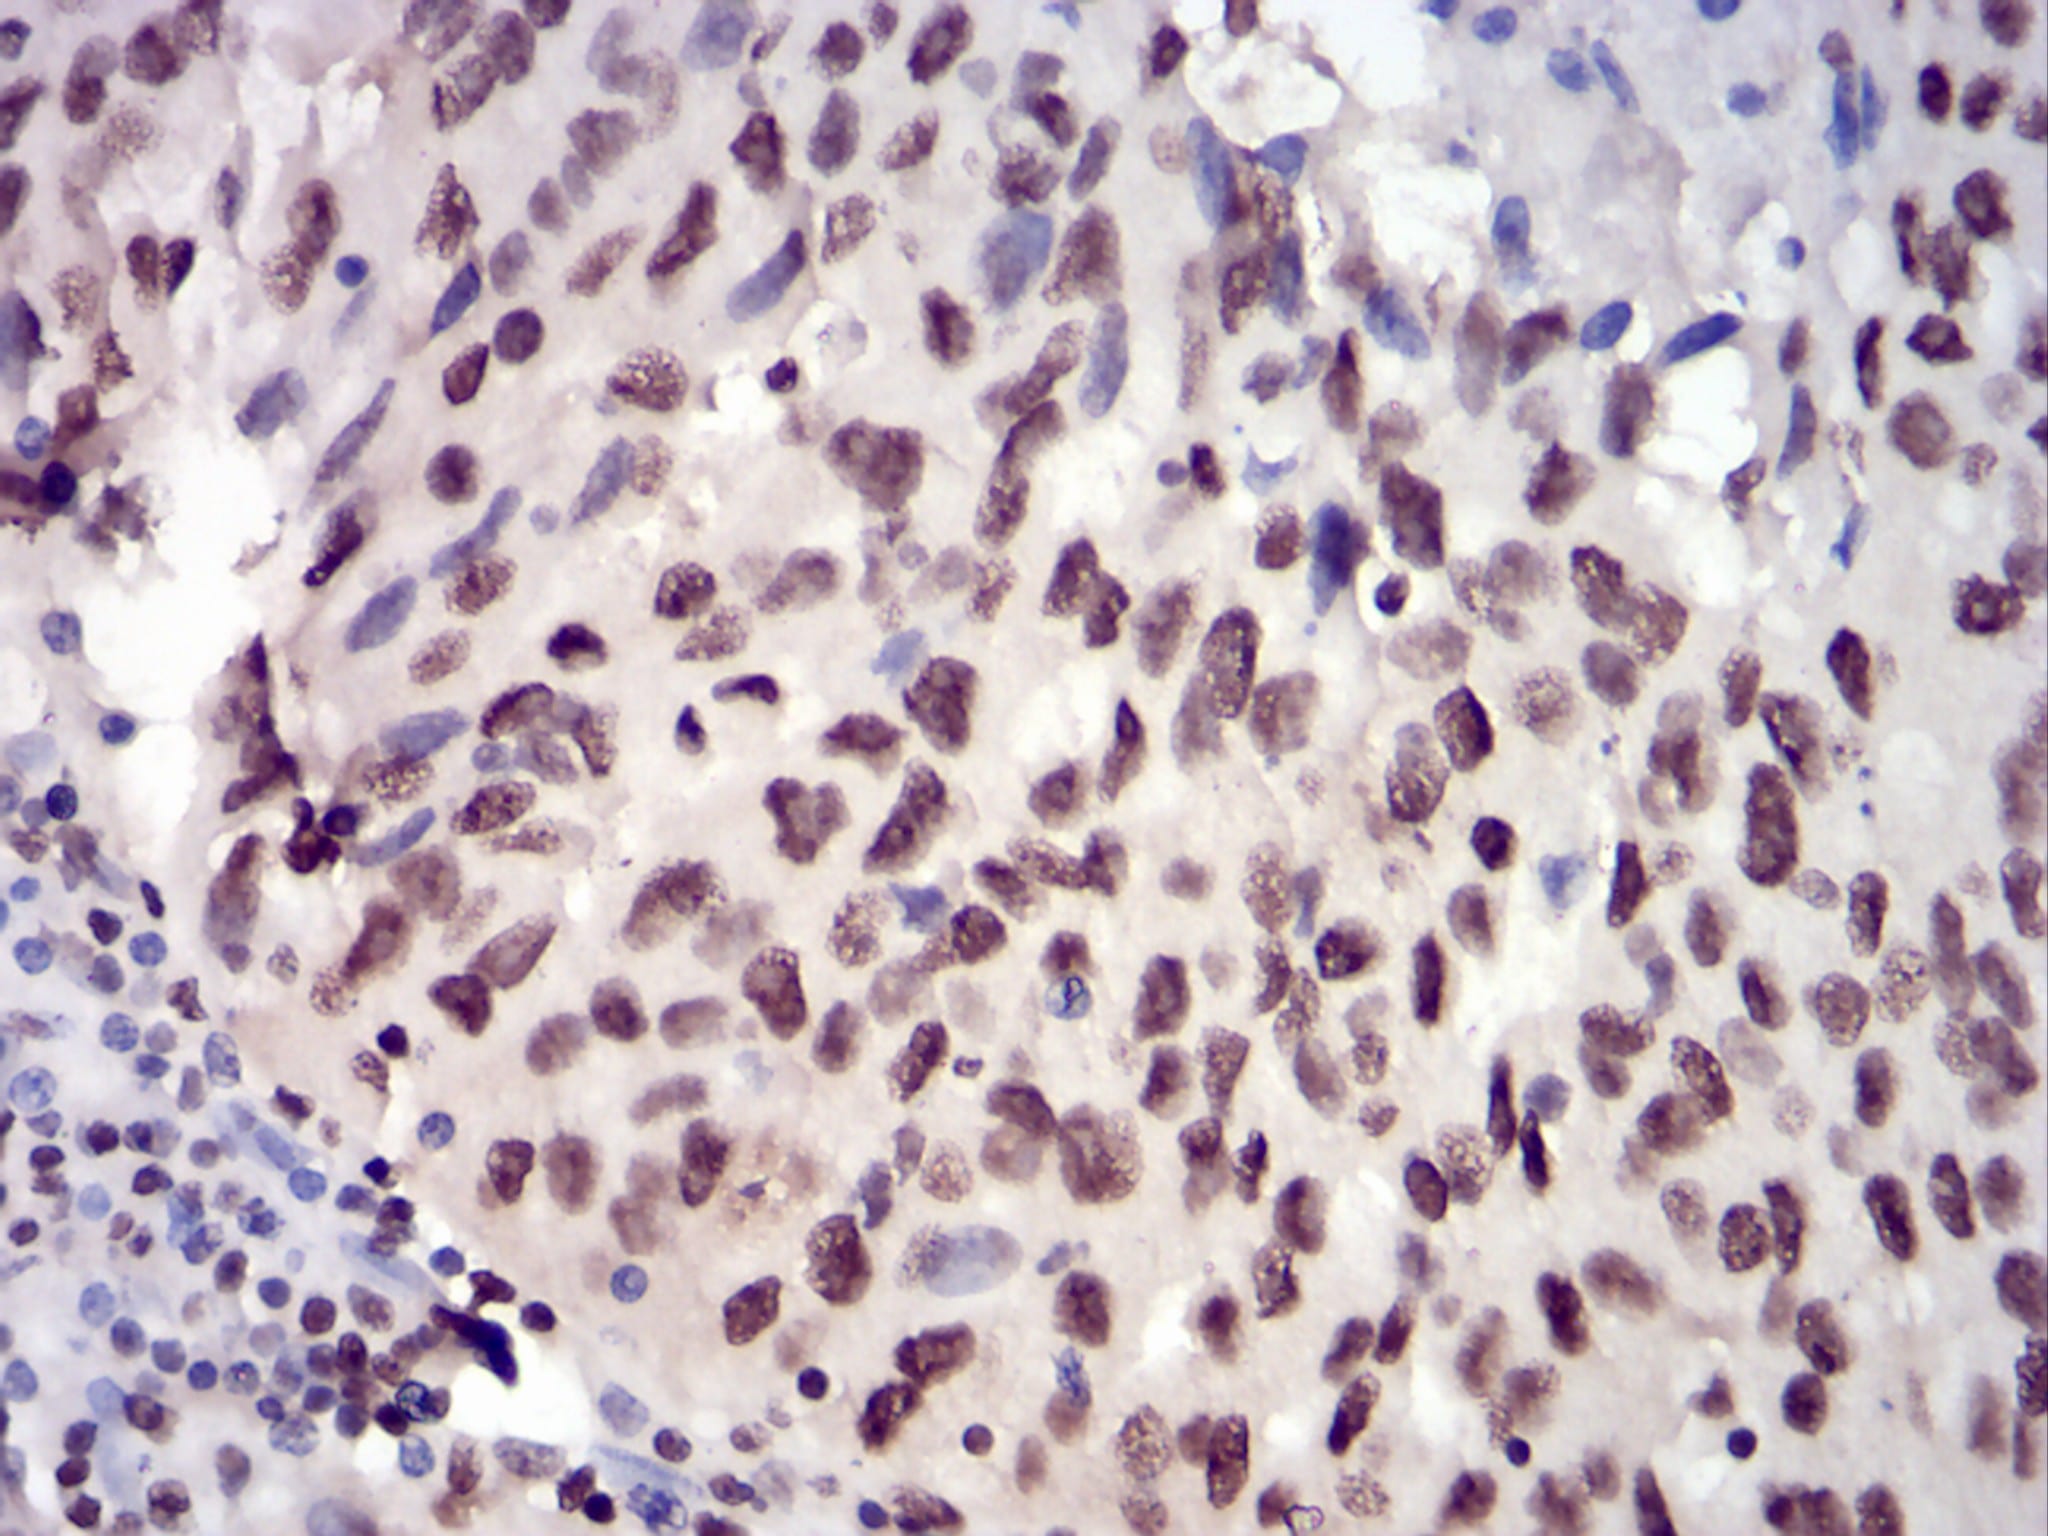

分类: 科研抗体货号: 30744别名: EIF-5A; EIF5A1; eIF5AI应用: IHC,FCM反应种属: Human